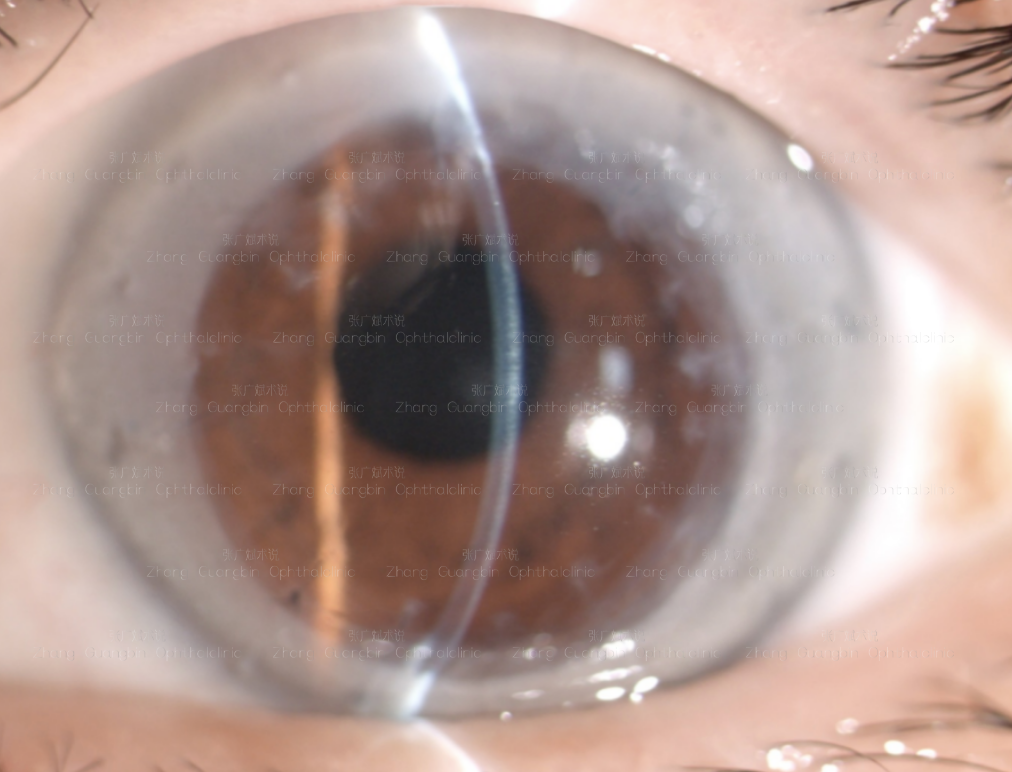

OS-Phaco+TORIC IOL(ZEISS 709m:+9DS/ +8.5DC 709@25°),预留近视

OS术后3个月:0.3(-1.0DS/-2.00DC×145→0.6) -

OPD :TORIC IOL(轴向约25°,无明显旋转),眼总散光-0.87@142° -

OPD验光:-1.79DS/-0.92DC×142°,与主觉验光中散光存在一定误差。